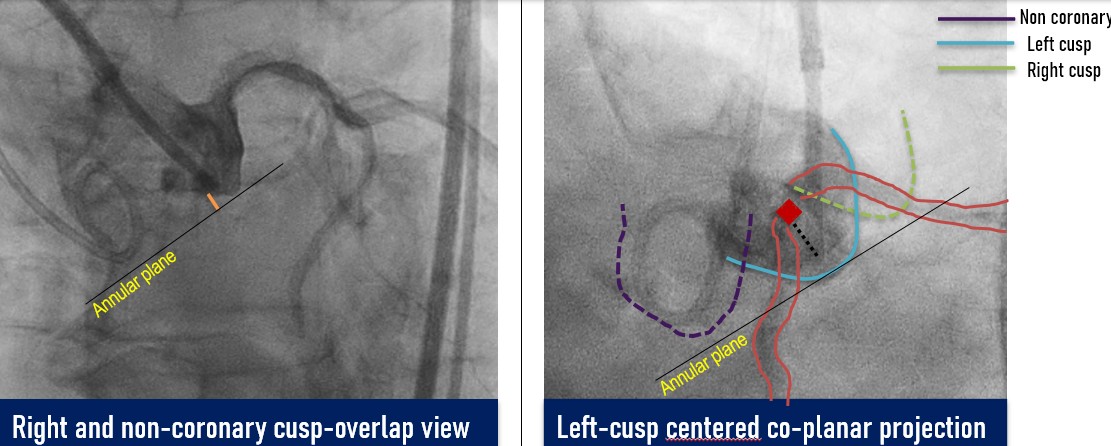

Coronary angiogram showed minor disease. Root angiography done to identify and isolate views for procedure

A controlled laceration of the native left coronary cusp was planned under general anaesthesia. A puncture point 2 mm above the cusp base, aligned with the coronary ostium, was selected to ensure optimal leaflet splay and minimise recoil risk following laceration. Leaflet traversal was performed using electrocautery at 50 W in pure-cut mode, delivered through a 0.014-inch, 300-cm Astato wire (ASAHI) advanced via a 150-cm Finecross microcatheter (Terumo), housed within a 6-French, 125-cm multipurpose diagnostic catheter and an 8-French Amplatz Left guide catheter. After advancing the microcatheter into the left ventricle, the Astato wire was exchanged for a 0.014-inch Fielder wire. Initial dilatation was performed using a 3 mm non-compliant Apollo balloon (BrosMed Medical). The Fielder wire was then exchanged for a 0.035-inch, 260-cm J-tip wire, and subsequently for a pre-shaped Safari wire (Boston Scientific). Based on procedural planning, a balloon size equal to or up to 2 mm shorter than the leaflet length was deemed adequate to achieve effective laceration while avoiding sinus or annular injury. Controlled leaflet laceration was performed using sequential balloon dilatations with an 8-mm Armada balloon (Abbott Cardiovascular) followed by a 12-mm Mustang balloon (Boston Scientific). Successful laceration was indicated by a sudden give-way of the balloon waist, inward balloon shift toward the lumen, and a drop in diastolic pressure. A balloon-expandable valve was implanted.